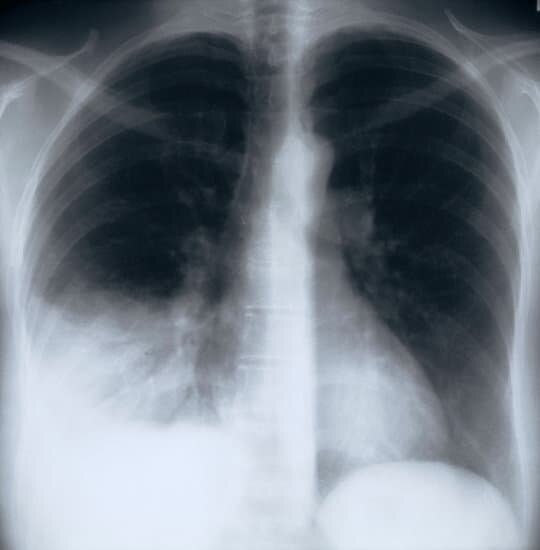

3. Рентген и КТ: наличие инфильтрации в легочной ткани.

Видна область затемнения в легких.